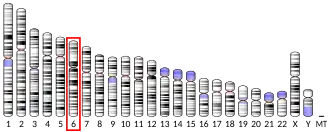

- ^ Levy FO, Holtgreve-Grez H, Taskén K, Solberg R, Ried T, Gudermann T (Aug 1994). "Assignment of the gene encoding the 5-HT1E serotonin receptor (S31) (locus HTR1E) to human chromosome 6q14-q15". Genomics. 22 (3): 637–40. doi:10.1006/geno.1994.1439. PMID 8001977.

- Levy FO, Holtgreve-Grez H, Taskén K, Solberg R, Ried T, Gudermann T (Aug 1994). "Assignment of the gene encoding the 5-HT1E serotonin receptor (S31) (locus HTR1E) to human chromosome 6q14-q15". Genomics. 22 (3): 637–40. doi:10.1006/geno.1994.1439. PMID 8001977.